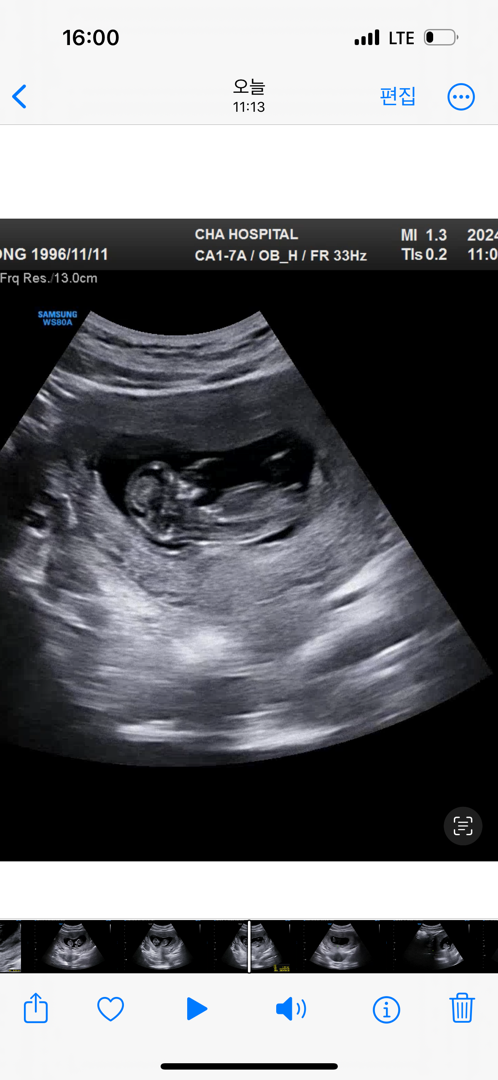

목투명대 정상 받고 궁금해진 성별 ㅎㅎ..

각도법 전 잘 모르겠더라구요 ㅠㅠㅋㅋㅋㅋㅋㅋ 그냥 16주 되면 알겠지 싶은데 궁금하네요 !!

저도 딸같아요!!

딸같은데용 ~.~